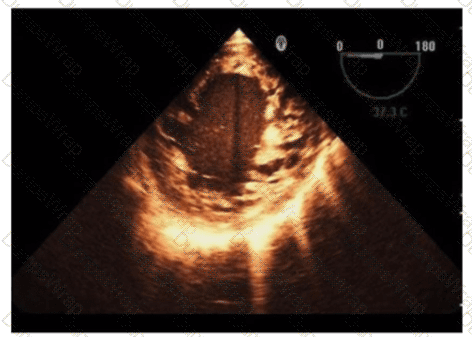

Which anatomic structure is represented by the arrow on this image?

Options:

Left leaflet

Posterior leaflet

Septal leaflet

D. Anterior leaflet

Answer:

DExplanation:

The echocardiographic image is a four-chamber view focusing on the mitral valve apparatus. The arrow points to the anterior leaflet of the mitral valve, which is typically more prominent, triangular in shape, and located adjacent to the aortic valve in the left ventricular outflow tract region.

The posterior leaflet of the mitral valve is generally smaller, has multiple scallops, and is located posteriorly relative to the anterior leaflet. The septal leaflet is part of the tricuspid valve on the right side of the heart. The "left leaflet" is a non-specific term and not an anatomical descriptor.

This differentiation between anterior and posterior leaflets is important for understanding mitral valve pathology and for interventions such as mitral valve repair. These features are clearly explained in echocardiography texts and ASE valve imaging guidelines【12:ASE Valve Imaging Guidelines†p.180-185】【16:Textbook of Clinical Echocardiography, 6e†p.200-205】.